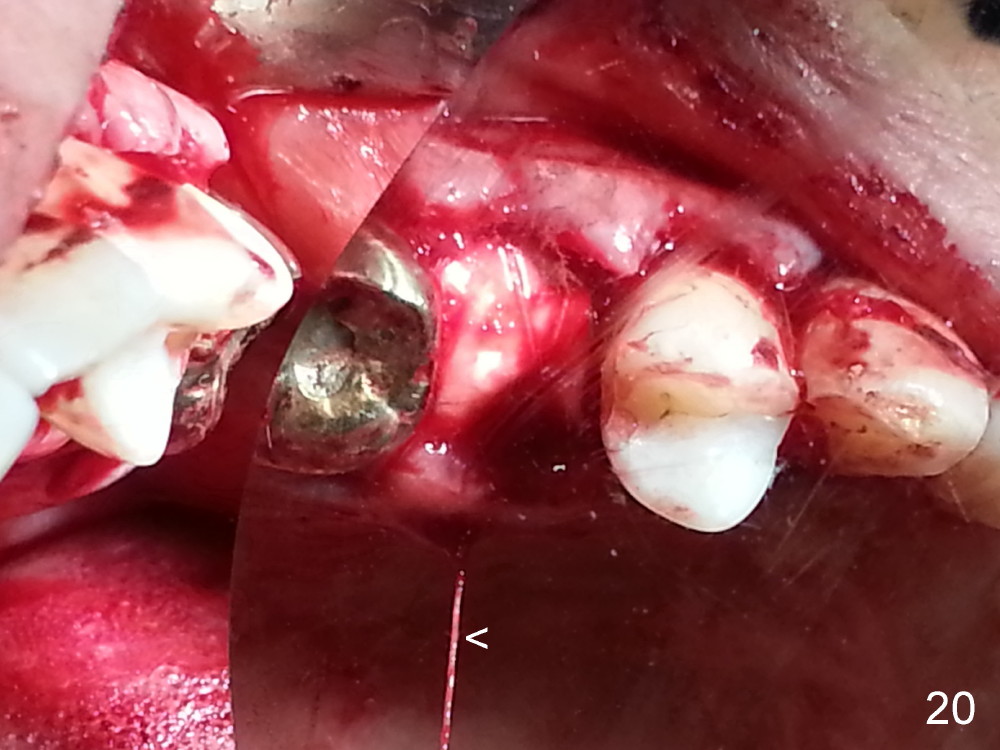

The tooth #13 appears to be affected by periodontits and occlusal trauma (Fig.1*). After using a periotome (Fig.2), the tooth is extracted (Fig.3). The buccal flap is raised (Fig.4). Gingival graft is to be harvested from the site of #15 (Fig.5). The tissue is elevated buccally (Fig.6) and separated (Fig.7). The donor site is covered by a collagen membrane (Fig.8*). A diamond bur is used to induce bleeding from the socket (Fig.9*). Osteotomy is initiated (Fig.10) and enlarged (Fig.11,12). A tapered implant is being placed (Fig.13-15) following internal sinus lift (Fig.16,17). The implant is placed subcrestally, followed by bone graft (Fig.18), soft tissue graft (Fig.19), and suturing (Fig.20 <, Fig.21).